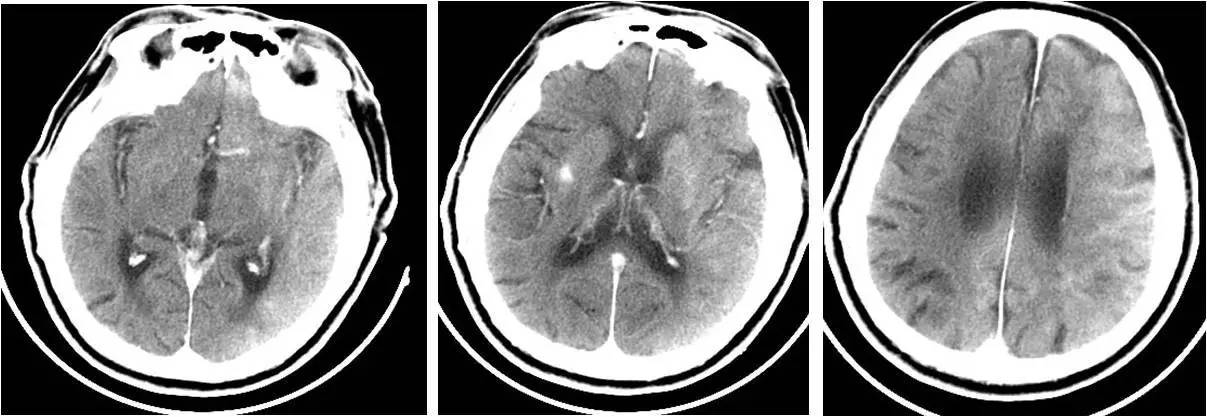

》术后10h出现发热,体温最高达38.8℃,无头痛,无恶心、呕吐,无肢体抽搐。查体:浅昏迷,双眼左侧凝视,右侧肢体肌张力低,疼痛刺激无反应,右侧巴氏征阳性。

诊断及治疗

文献报道3例,均因头晕及无脉症就诊。

表现为可逆性后部脑白质综合征、丘脑出血、枕叶出血。